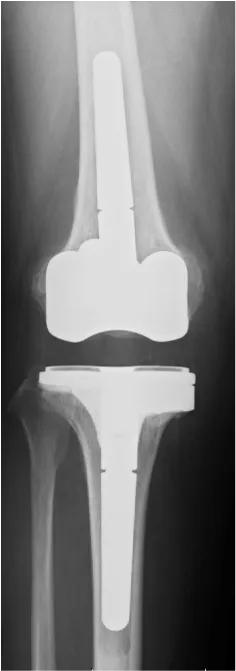

人工膝関節置換術

人工膝関節置換術は、傷んだ関節表面を切除し、金属やセラミック、ポリエチレンなどで作られた人工の関節に置き換える手術です。虫歯を削って被せ物をするような手術です。現在日本では年間9万件以上行われているといわれています。

近年、人工膝関節置換術は、人工関節自体のデザインや素材が飛躍的に良くなり、また手術方法の発達により、15〜20年以上長期間でも約90%が入れ替えを必要としないで済むと報告されています。

• O脚膝 術前

• 人工関節置換術後